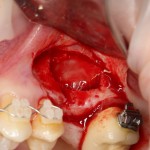

В ходе проведения операции синуслифтинга, у нас образовалась небольшая перфорация шнайдеровой мембраны:

Мы начинаем с того, что выводим ее в центр апертуры, попутно мобилизуем края. В результате, она несколько уменьшилась в размерах:

Чем бы ее заклеить?

В данном случае я использовал Geistlich Mucograft Seal 8mm. Биоматериал в данном форм-факторе стоит дешевле, чем барьерная мембрана, а его диаметр позволяет легко перекрыть образовавшийся дефект слизистой:

Перед позиционированием Mucograft лучше намочить. Он станет более эластичным (без потери прочности) и мягким:

После чего, он легко приклеивается и перекрывает дефект:

Нам лишь остается заполнить образовавшееся субантральное пространство графтом (Bio-Oss) и закончить операцию синуслифтинга и остеопластики так, как мы планировали: